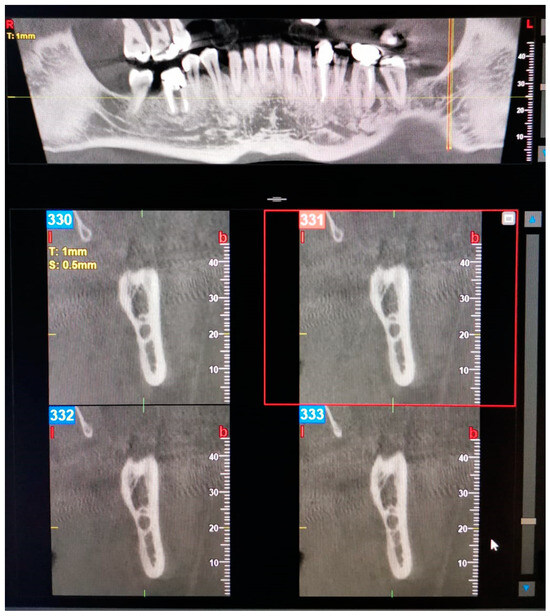

Figure 6. Panoramic view and transverse section of a left TMC. l, lingual. b, buccal. T, thickness. S, section.